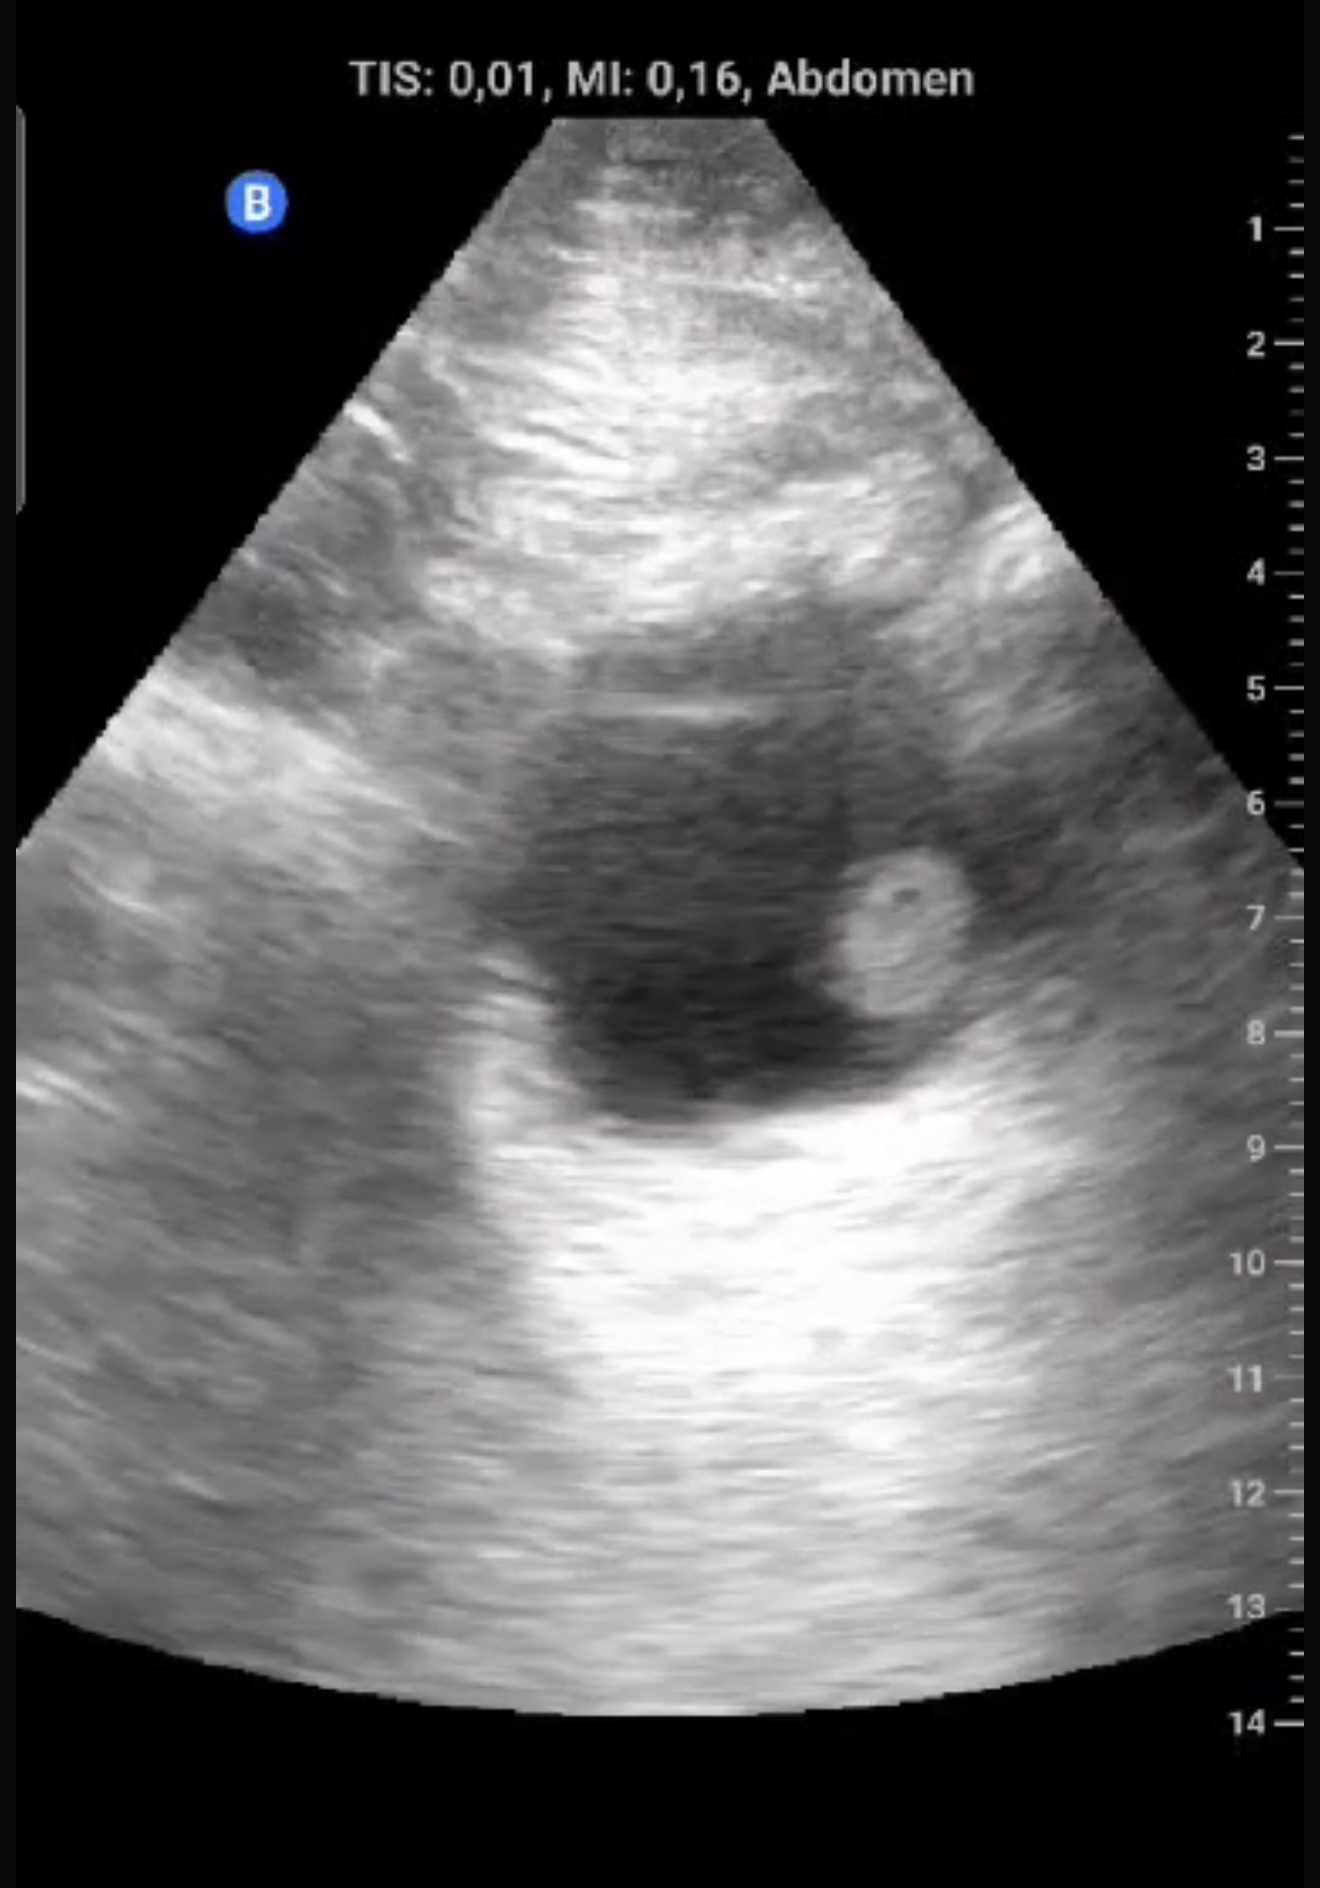

Exfumador, HTA, hipercolesterolemia, cirrosis hepática por alcohol. Hombre de 58 años que refiere episodio de hematuria macroscópica hace dos semanas, coincidiendo con un esfuerzo físico intenso el día previo. No presenta disuria, fiebre, poliaquiuria, ni dolor. En controles posteriores, no había recurrencia de hematuria y el paciente se encontraba asintomático.Exploración física sin hallazgos relevantes. Ecografía realizada en consulta en apenas 5 minutos mostró una masa en la cara lateral izquierda de la vejiga, de 1,5 x 1,3 cm, con características sugerentes de lesión tumoral superficial.

Lesión sólida, pediculada, de bordes definidos y fronda larga en la cara lateral izquierda de la vejiga.

Se sospechó un tumor vesical; pólipo vesical. Urología confirmó la lesión mediante cistoscopia, describiendo una masa papilar superficial de 2 cm en la pared lateral izquierda.